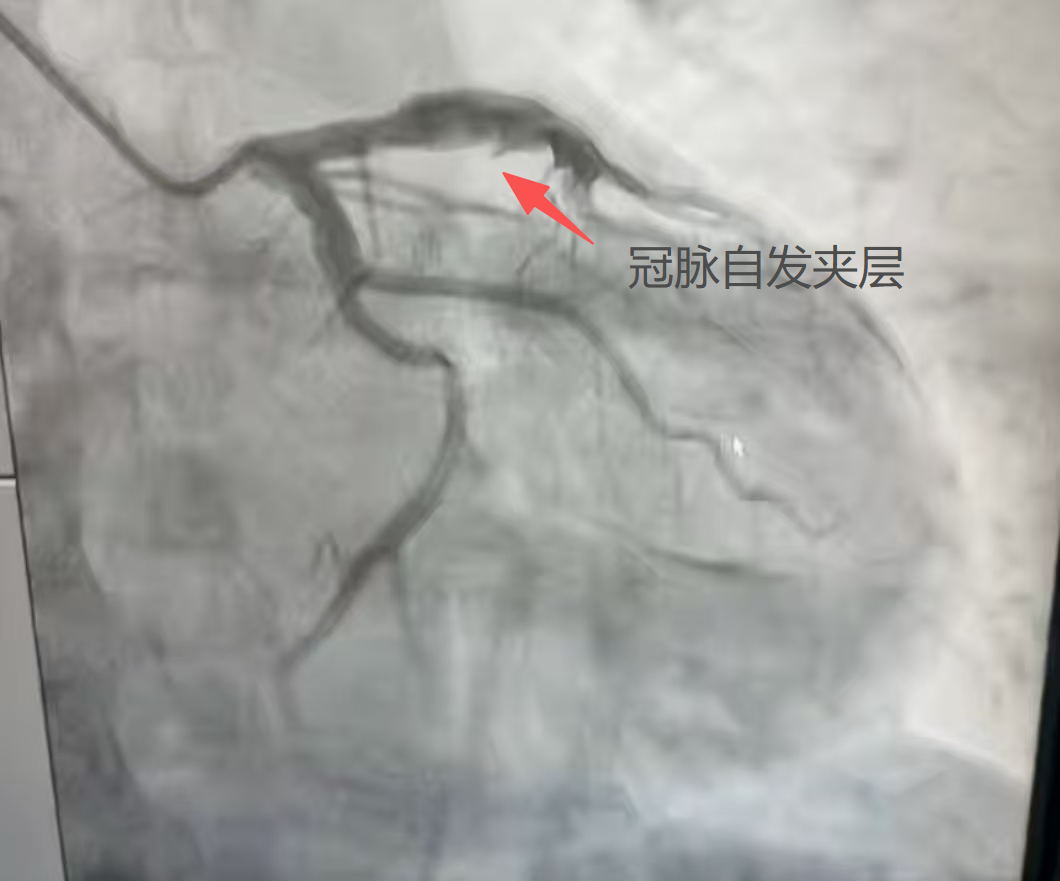

很快,姜先生被医护人员推入了急诊介入室。心血管科副主任医师张竹华、主治医师张振民迅速为姜先生完善了冠状动脉造影检查。结果提示姜先生左前降支近段管腔异常粗大,并伴有自发夹层形成;为充分评估血管情况,通过冠状动脉血管内超声(IVUS)检查,确认了姜先生本次心肌梗死就是因为冠脉自发夹层导致的,且左前降支近段异常粗大,最大直径已超过8mm。

冠脉造影提示左前降支近段管腔粗大伴自发夹层